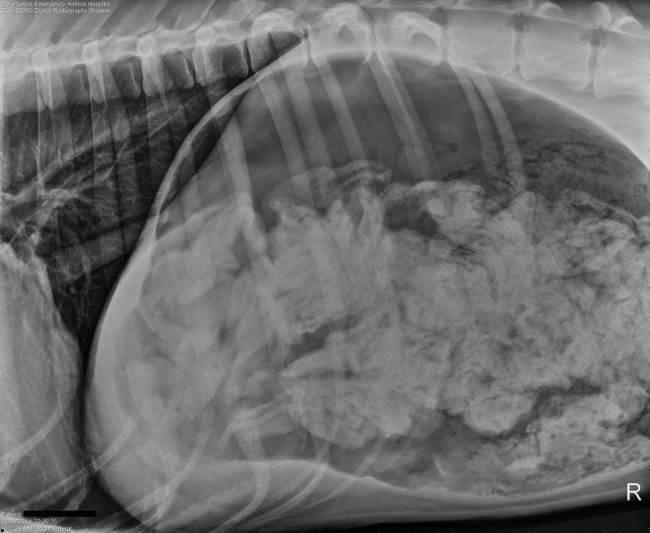

Το καημένο το σκυλί δεν μπορούσε να αναπνεύσει καλά ενώ είχε τάση για εμετό...

Οι ιδιοκτήτες του σκύλου το μετέφεραν αμέσως στην κλινική προκειμένου να του γίνουν οι απαραίτητες εξετάσεις.

Τελικά αποδείχτηκε ότι το σκυλί είχε μέσα στο στομάχι του ένα μικρό θησαυρό από... 43 κάλτσες!

Χρειάστηκε μία επέμβαση διάρκειας δύο ωρών για να μπορέσει να καθαριστεί το στομάχι του σκύλου ράτσας Great Dane (Μεγάλος Δανός αν προτιμάτε).

Προφανώς ο μεγαλόσωμος σκύλος το είχε δει σαν παιχνίδι να μασουλάει τις κάλτσες του αφεντικού του και στο τέλος τις κατάπινε!

Δείτε τις εικόνες